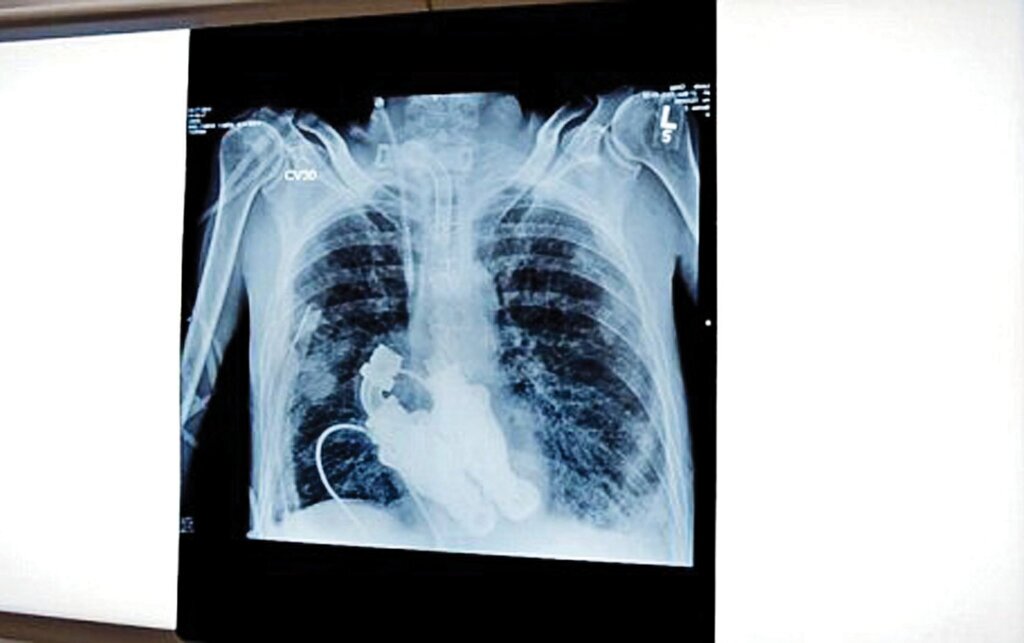

کرگ در بخش مراقبت‌های ویژه بستری بود. هریک از پزشکان به نوبت گوشی طبی را روی سینه کرگ می‌گذاشتند، اما هیچ صدای ضربان قلبی به گوش نمی‌رسید و تنها صدایی مثل وزوز از سینه کرگ به گوش می‌رسید. گوشی طبی به لیندا همسر کرگ داده شد. او درباره این لحظه هیجان‌انگیز و باورنکردنی می‌گوید: «من با دقت گوش کردم، فقط صدای وزوز می‌آمد. باورنکردنی بود. او هیچ ضربان قلبی نداشت. چون هیچ قلبی نداشت.»